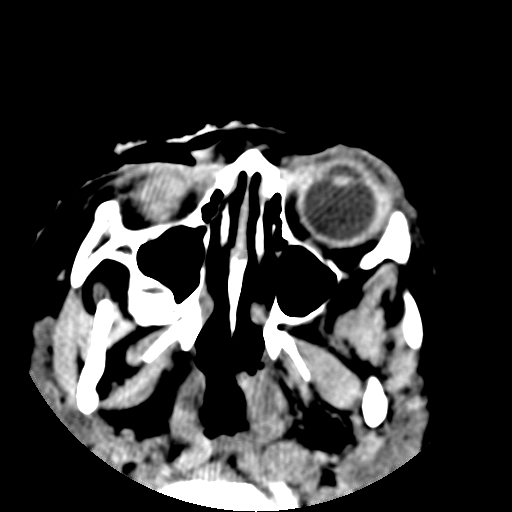

以下是引用深泽交通医院在2009-10-16 8:25:00的发言:[br]右眼环出血伴异物

以下是引用卜一在2009-10-16 15:01:00的发言:[br]右眼球挫裂伤伴异物!

以下是引用拾荒者在2009-10-17 18:38:00的发言:[br]鼻面部皮下积气,右侧睑缘及眼球壁高密度异物影,左侧眼球壁晶状体内侧缘处是圆形低密度影。低密度异物?应提请眼科医生注意。